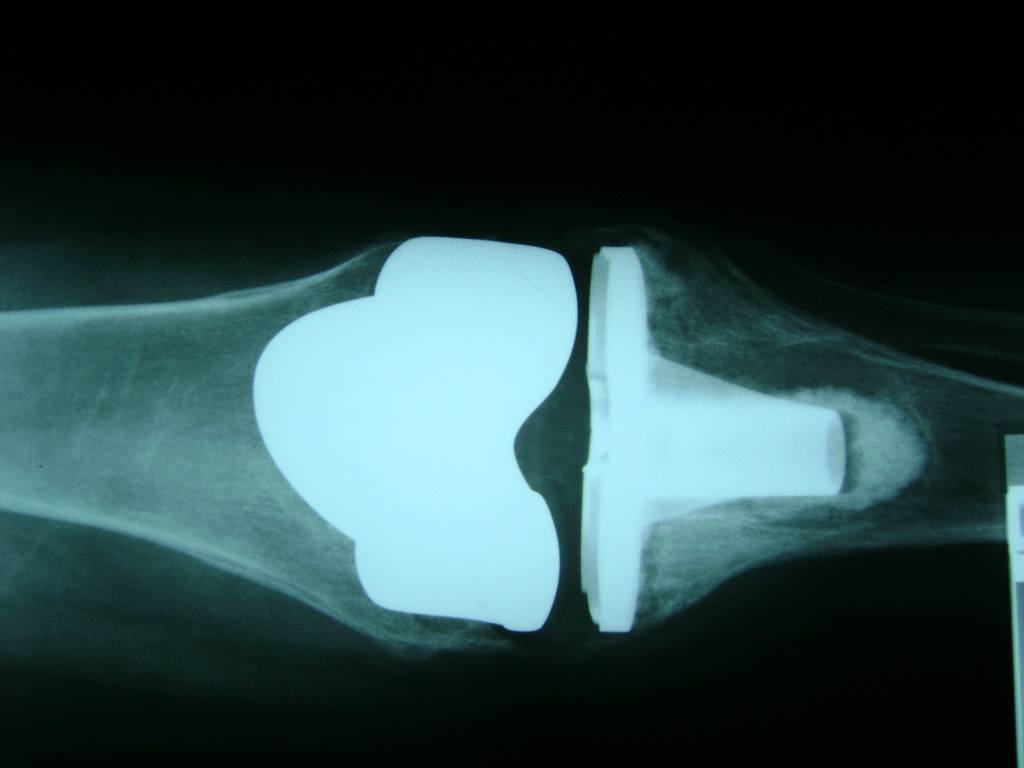

Cirugías de Calcaneo - Rodilla